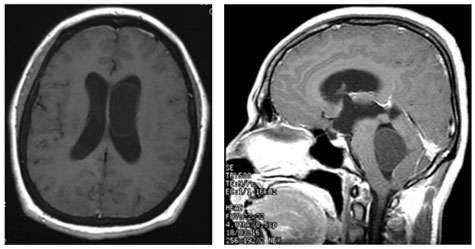

- When cysticercosis affects the brain or spinal cord, the condition is called neurocysticercosis. Usually, the cyst causes inflammation in the brain tissue itself which results in a seizure. In about 10% of neurocysticercosis cases, the cysts are found within the cerebral ventricles or in the cerebrospinal fluid spaces (cisterns). This can cause hydrocephalus or symptoms due to pressure on the brain.

- In about 10 percent of neurocysticercosis cases the cysts are found within the cerebral ventricles or in the cerebrospinal fluid spaces (cisterns). This can cause hydrocephalus or symptoms due to pressure on the brain.

- Cisternal cysts can act like brain tumors, causing symptoms due to compression of the brain. The symptoms will depend upon which part of the brain is affected.

- Diagnosis is best made by magnetic response imaging (MRI), although intraventricular cysts can sometimes be very difficult to detect on routine MRI imaging.